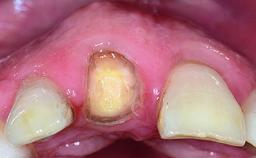

Replacement of a Failing Upper Left Central Incisor: Immediate Placement of an RC Bone Level Implant and Provisionalization

A healthy 23-year-old female patient was referred for a consultation on replacing tooth 21 with an implant-supported restoration. The patient had recently moved to the area and reported a history of endodontic and periodontal treatment for tooth 21. The tooth had been deemed non-restorable by her previous periodontist but since she was going to be moving, he recommended consulting to a dentist in her new city to continue her treatment. A review of her medical history yielded no significant findings and no known drug allergies. The analysis of her smile revealed a medium to high symmetrical smile line and a slightly discolored tooth 21.

Abutment Type CAD/CAM

Prosthesis Type FDP

Loading Protocol Immediate

Provisional Implant-Supported Prosthesis Prosthodontic margin < 3 mm apical to mucosal margin Prosthodontic margin < 3 mm apical to mucosal margin